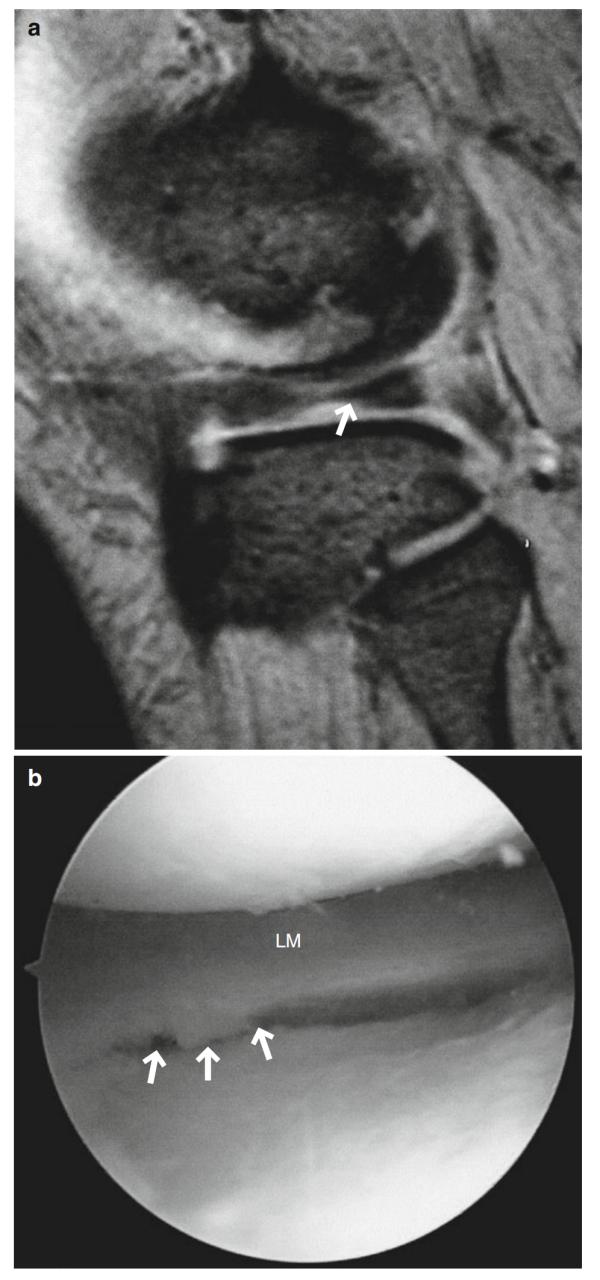

图7.21非常小的半月板撕裂。60多岁的女性。(a ) T2*WI和(b)关节镜成像。在外侧半月板(LM)的下表面有一个小的阶梯状外观(箭头,a)。关节镜下可见半月板游离边缘不规则和下表面纤维化(箭头,b)